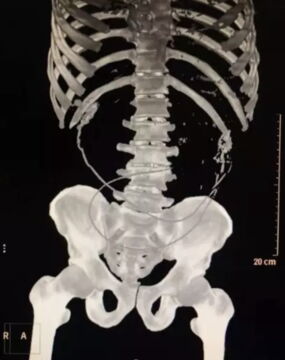

The man reported to Dongguan Huangjiang Hospital in Guangdong in China complaining of stomach pains.According to the head of general surgery Li Jian the man had severe sepsis leading to septic shock and could not communicate coherently. Doctor Li stated:

He came in with septic shock. During a CT scan, we suspected a foreign body in his abdominal cavity, but we couldn't tell what it was. Then while performing a colonoscopy, we discovered it was an Asian swamp eel (monopterus albus). It had entered his abdominal cavity.

An image taken by the surgeons shows a shocking 40cm long freshwater eel still very much intact but very much dead. Dr Li said:

It was already dead. But it caused severe bacterial contamination in his abdomen due to a build-up of faeces and pus. It was only after surgery, when we were enquiring after his medical history, that he told us he used the eel to cure his constipation. He inserted it up his anus into his rectum. I suspect it was then that the perforation in his sigmoid colon occurred.